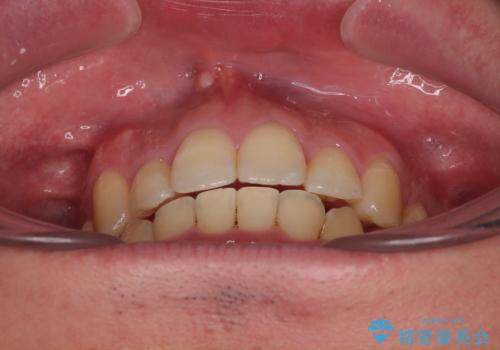

- デコボコと前歯の突出感を気にして来院された患者様です。

舌の突出癖などにより上顎前歯が前方に突出し、さらに歯列幅が狭小になっている状態でした。

また、上顎歯列全体が下顎に対して前方位に位置していました。